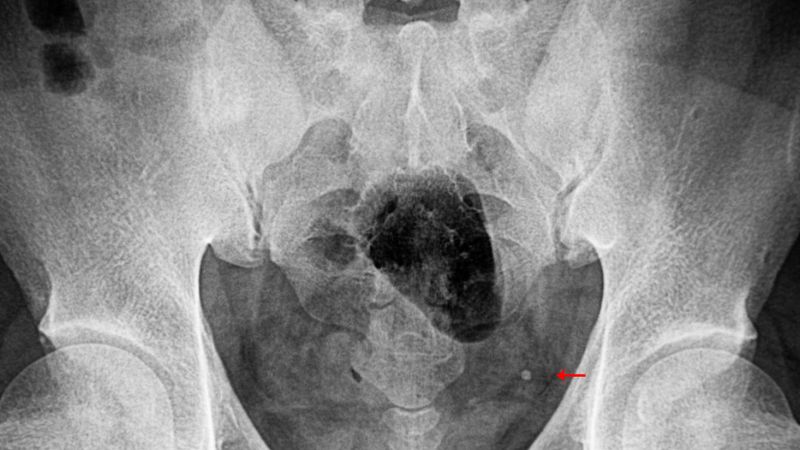

Nhận biết triệu chứng sỏi niệu quản và cách điều trị hiệu quả 1

Sỏi niệu quản là những viên đá nhỏ hình thành trong niệu quản